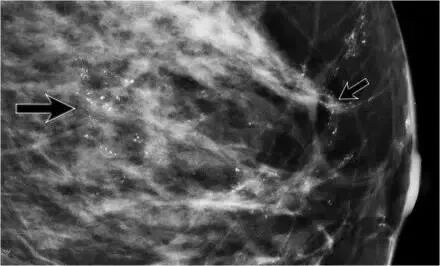

乳腺癌的分类中,有一个大类叫做乳腺导管原位癌(DCIS),也被称作是0期癌,这是一种在理论上不会发生转移的肿瘤。 有的医生在看诊的时候会跟病人说:原位癌是一种不是癌的癌,这种肿瘤连重疾险都不予覆盖。很多患者就误解为:这不是什么严重的事情,以为得了“0期癌”就可以不用治疗,或者轻治疗。 那么,原位癌是不是真的吃吃药就可以万无一失了呢? 肿瘤的诊断金标准一般是组织病理活检,就是将穿刺/手术取得的肿瘤组织标本拿去进行病理检查,以确认肿瘤的性质。 乳腺导管原位癌作为乳腺恶性肿瘤的一种,自然也需要通过影像学和病理(穿刺/手术)来明确诊断。 原位癌最为特征的影像学表现,就是钼靶片上会出现星星点点的钙化。这种钙化的主要特点是:呈细小的线性。从片子上可以看到一堆堆,一条条的钙化线。这符合导管原位癌的一个特性-“导管内生长”,所以钙化线会呈现出导管的形状轮廓。 钼靶影像 乳腺导管原位癌在理论上是不会发生转移的。那是不是可以不用遭受手术的一刀之苦呢? 导管原位癌的治疗手段一直以来都争议不断。是否进行手术?该采取何种手术方式?是争论的要点。是否过度治疗?如何避免过度治疗又不会导致治疗不足?也是乳腺专家们一直关心的重要问题。 2020年5月,《肿瘤外科学报》发表了哈佛大学麻省总医院关于乳腺导管原位癌DCIS术后病理存在浸润成分(IDC)的一项研究报告。该研究记录了2007-2016年10年间该院858例DCIS女性患者,研究结果表明: 即使在密切监测条件下入组的DCIS患者,仍然有隐匿性乳腺浸润癌的风险。 在858位患者中,不同分组的患者,共计103例发现了肿瘤包含了可发生转移的浸润成分,比例在5%~12%之间。 而实际临床中我们也能发现:原位癌患者术后病理检出浸润癌的比例可以高达50%。就是说:穿刺并不能反映肿瘤的全面性质,大部分的原位癌其实都不纯洁。掺杂了浸润癌的患者,需要按照乳腺浸润性癌的诊疗标准来加强治疗。 很多原位癌患者对手术方式抱有疑问的态度: 这其实是由原位癌的生长特点决定的。大部分的原位癌,在较早的时候是触摸不到的,或者触诊的感觉跟常见的肿块类似,使得很多患者都忽略了筛查,最终导致发现的时候,肿瘤已经长得比较大块。 而原位癌沿着导管生长的特点,也让手术中边缘阴性(指手术意义上全部切除干净)变得比较困难。因此,4cm以下的原位癌还可以尝试做保乳手术;而超过4cm的肿瘤,因为长了很多“螃蟹腿”,难以达到边缘阴性,通常会选择全乳切除。 上图为边缘阳性/阴性加放疗与全切后随访结果的对比。 其中,边缘阴性和切乳在3年内再发风险没有差别 研究指出:手术的时候“切干净”,能有效降低原位癌再发为浸润癌的风险(下图是边缘阳性/阴性加放疗与全切后随访结果的对比,其中,边缘阴性和切乳在3年内再发风险没有差别)。同时,考虑部分患者存在浸润成分,前哨淋巴结活检也是个必不可少的步骤。 不过,尽管不少患者需要做全乳切除,但如果肿瘤没有侵蚀到乳头的位置,还是可以考虑保留乳头的乳腺皮下切除+假体重建,来保持乳房的形状,避免“切乳”后的多种问题。 尽管0期癌的复发风险相对较低,但是充足的治疗是保证未来健康最基本的保证。 由于导管原位癌对化疗并不敏感,所以在术后病理排除了浸润癌成分可能后,可以免除化疗。对可疑高危的分型,可按照主治医生建议,接受“基础档次”的化疗进行加强治疗。 美国国家癌症研究所(NCI)的研究结果表明:无论是低中高危的导管原位癌患者,放疗后的复发比例都有显著下降。尤其是对于低风险的患者,放疗降低风险的作用可以达到50%以上! 因此,放疗是保乳术后患者必不可少的一个重要治疗手段。除去放疗以外,内分泌治疗也是一个重要的健康保障。 内分泌治疗主要适合于激素受体阳性(ER/PR阳性)的患者,通过口服内分泌治疗,年轻患者(尚未绝经)还需综合考虑是否行去势治疗GnRha(打肚皮针绝经)。而激素受体阴性的患者,因内分泌治疗无效,故可免除。 诚然,即使是0期癌,乳腺导管原位癌也是恶性肿瘤的一种。面对癌症,恐惧和悲伤都是正常的心理状态。 《流浪地球》里有一句非常稚嫩但是非常适合各位病友的一句独白: 希望是这个世界上像钻石一样珍贵的东西。 乳腺导管原位癌的预后在所有乳腺癌类型中是最好的,其发展为浸润性癌的可能性较正常人罹患乳腺癌的可能性还低。 所以,要积极面对、坚持治疗、定期复查、做好康复。毕竟,0期癌是最容易被治愈的肿瘤之一。 希望,就是对生活最美好的点缀,也是对抗疾病最犀利的武器! 参考文献 [1] Tawakalitu O. Oseni, Barbara L. Smith, Constance D. Lehman, Charmi A. Vijapura, Niveditha Pinnamaneni, Manisha Bahl. Do Eligibility Criteria for Ductal Carcinoma In Situ (DCIS) Active Surveillance Trials Identify Patients at Low Risk for Upgrade to Invasive Carcinoma? Ann Surg Oncol. 2020 May 16. [Epub ahead of print] [2] Gurdeep S Mannu, Zhe Wang, John Broggio, Jackie Charman, Shan Cheung, Olive Kearins, David Dodwell, Sarah C Darby. Invasive breast cancer and breast cancer mortality after ductal carcinoma in situ in women attending for breast screening in England, 1988-2014: population based observational cohort study. BMJ. 2020 May 27;369:m1570. [3] Yang L, Lu D, Lai Y, Shen M, Yu Q, Lei T, Pu T, Bu H. Prognostic Score-Based Stratification Analysis Reveals Universal Benefits of Radiotherapy on Lowering the Risk of Ipsilateral Breast Event for Ductal Carcinoma In Situ Patients with Different Risk Levels. Ann Surg Oncol. 2020 Aug 13. Online ahead of print.乳腺导管原位癌(DCIS)的诊断